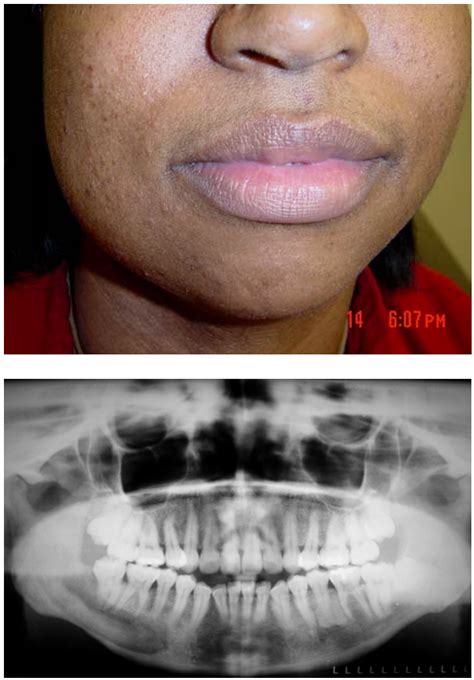

Bony lesions refer to any abnormal growths, defects, or changes in the bone tissue. These lesions can be benign (non-cancerous) or malignant (cancerous) and can occur in any part of the skeletal system. They are often detected through imaging techniques such as X-rays, CT scans, MRI, or bone scans. The characteristics of bony lesions can vary widely, making accurate diagnosis essential for appropriate treatment.

• Imaging Studies: X-rays, CT scans, MRI, and bone scans are commonly used to visualize the lesion and determine its characteristics.

• bony lesions of the mandible